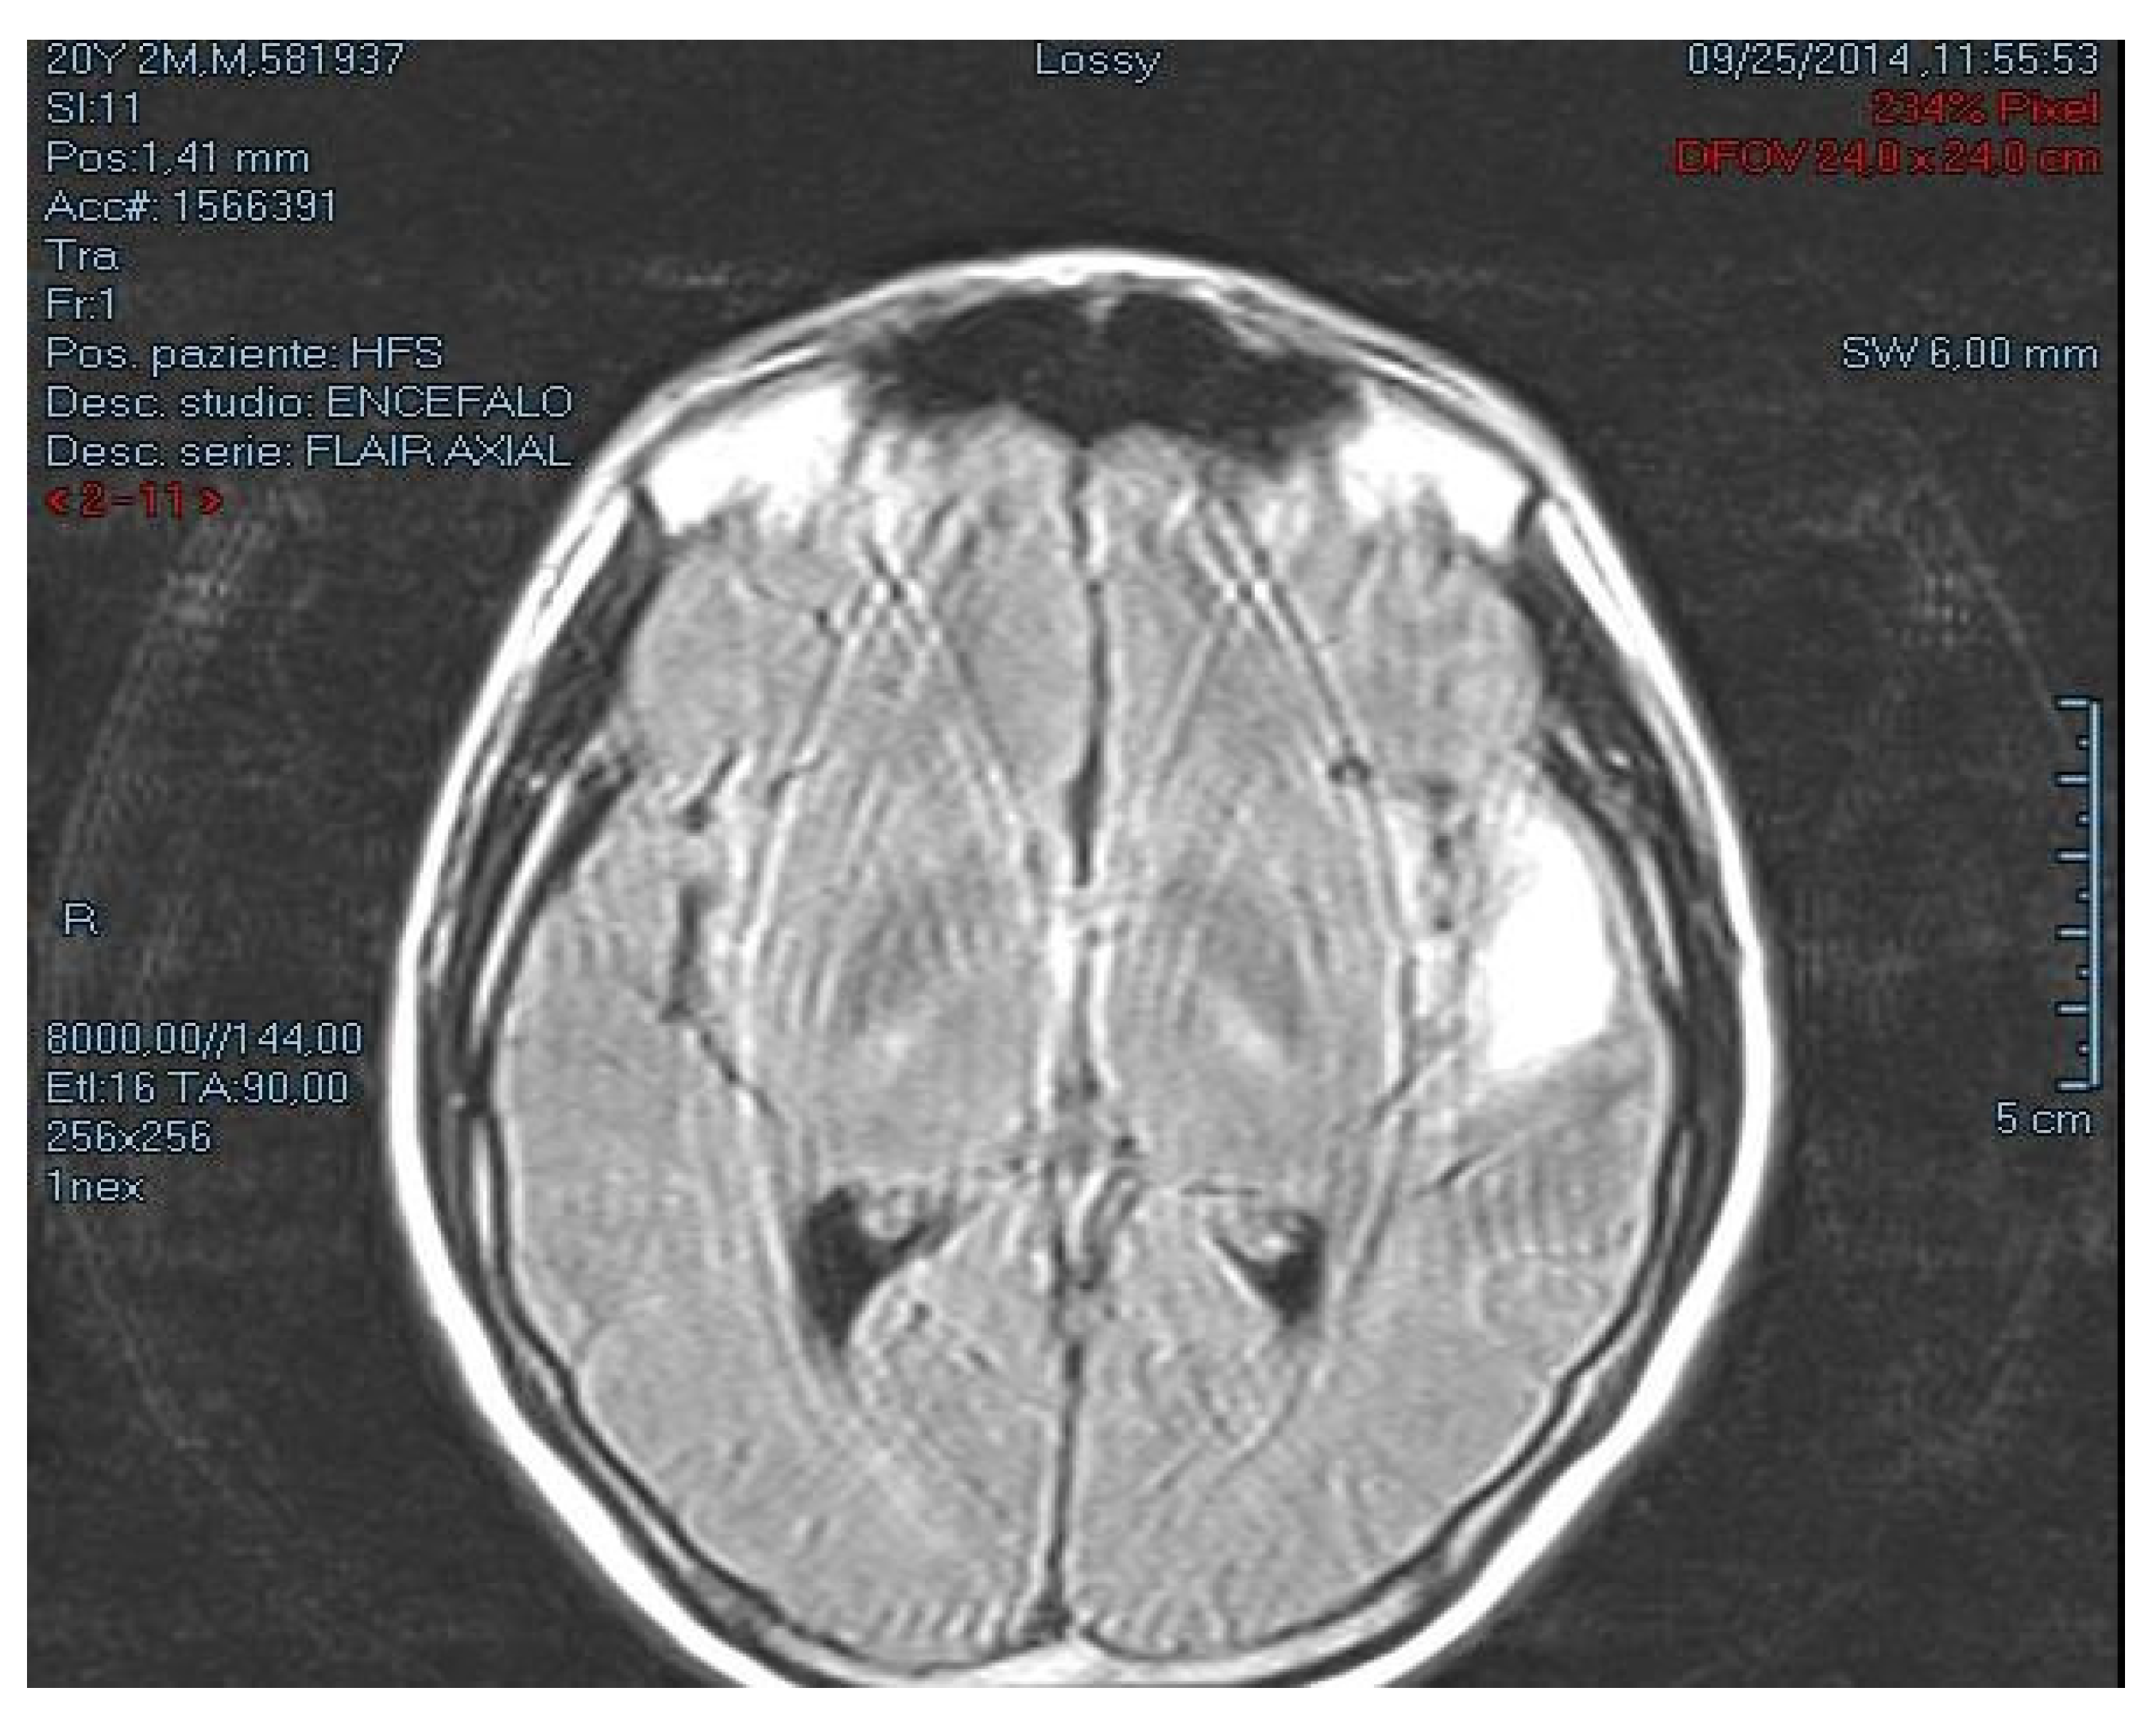

2.1. Case Description

2.2. Autopsy Findings